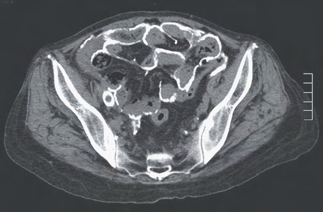

Recent studies indicate that Generative Pre-trained Transformer 4 with Vision (GPT-4V) outperforms human physicians in medical challenge tasks. However, these evaluations primarily focused on the accuracy of multi-choice questions alone. Our study extends the current scope by conducting a comprehensive analysis of GPT-4V's rationales of image comprehension, recall of medical knowledge, and step-by-step multimodal reasoning when solving New England Journal of Medicine (NEJM) Image Challenges - an imaging quiz designed to test the knowledge and diagnostic capabilities of medical professionals. Evaluation results confirmed that GPT-4V outperforms human physicians regarding multi-choice accuracy (88.0% vs. 77.0%, p=0.034). GPT-4V also performs well in cases where physicians incorrectly answer, with over 80% accuracy. However, we discovered that GPT-4V frequently presents flawed rationales in cases where it makes the correct final choices (27.3%), most prominent in image comprehension (21.6%). Regardless of GPT-4V's high accuracy in multi-choice questions, our findings emphasize the necessity for further in-depth evaluations of its rationales before integrating such models into clinical workflows.